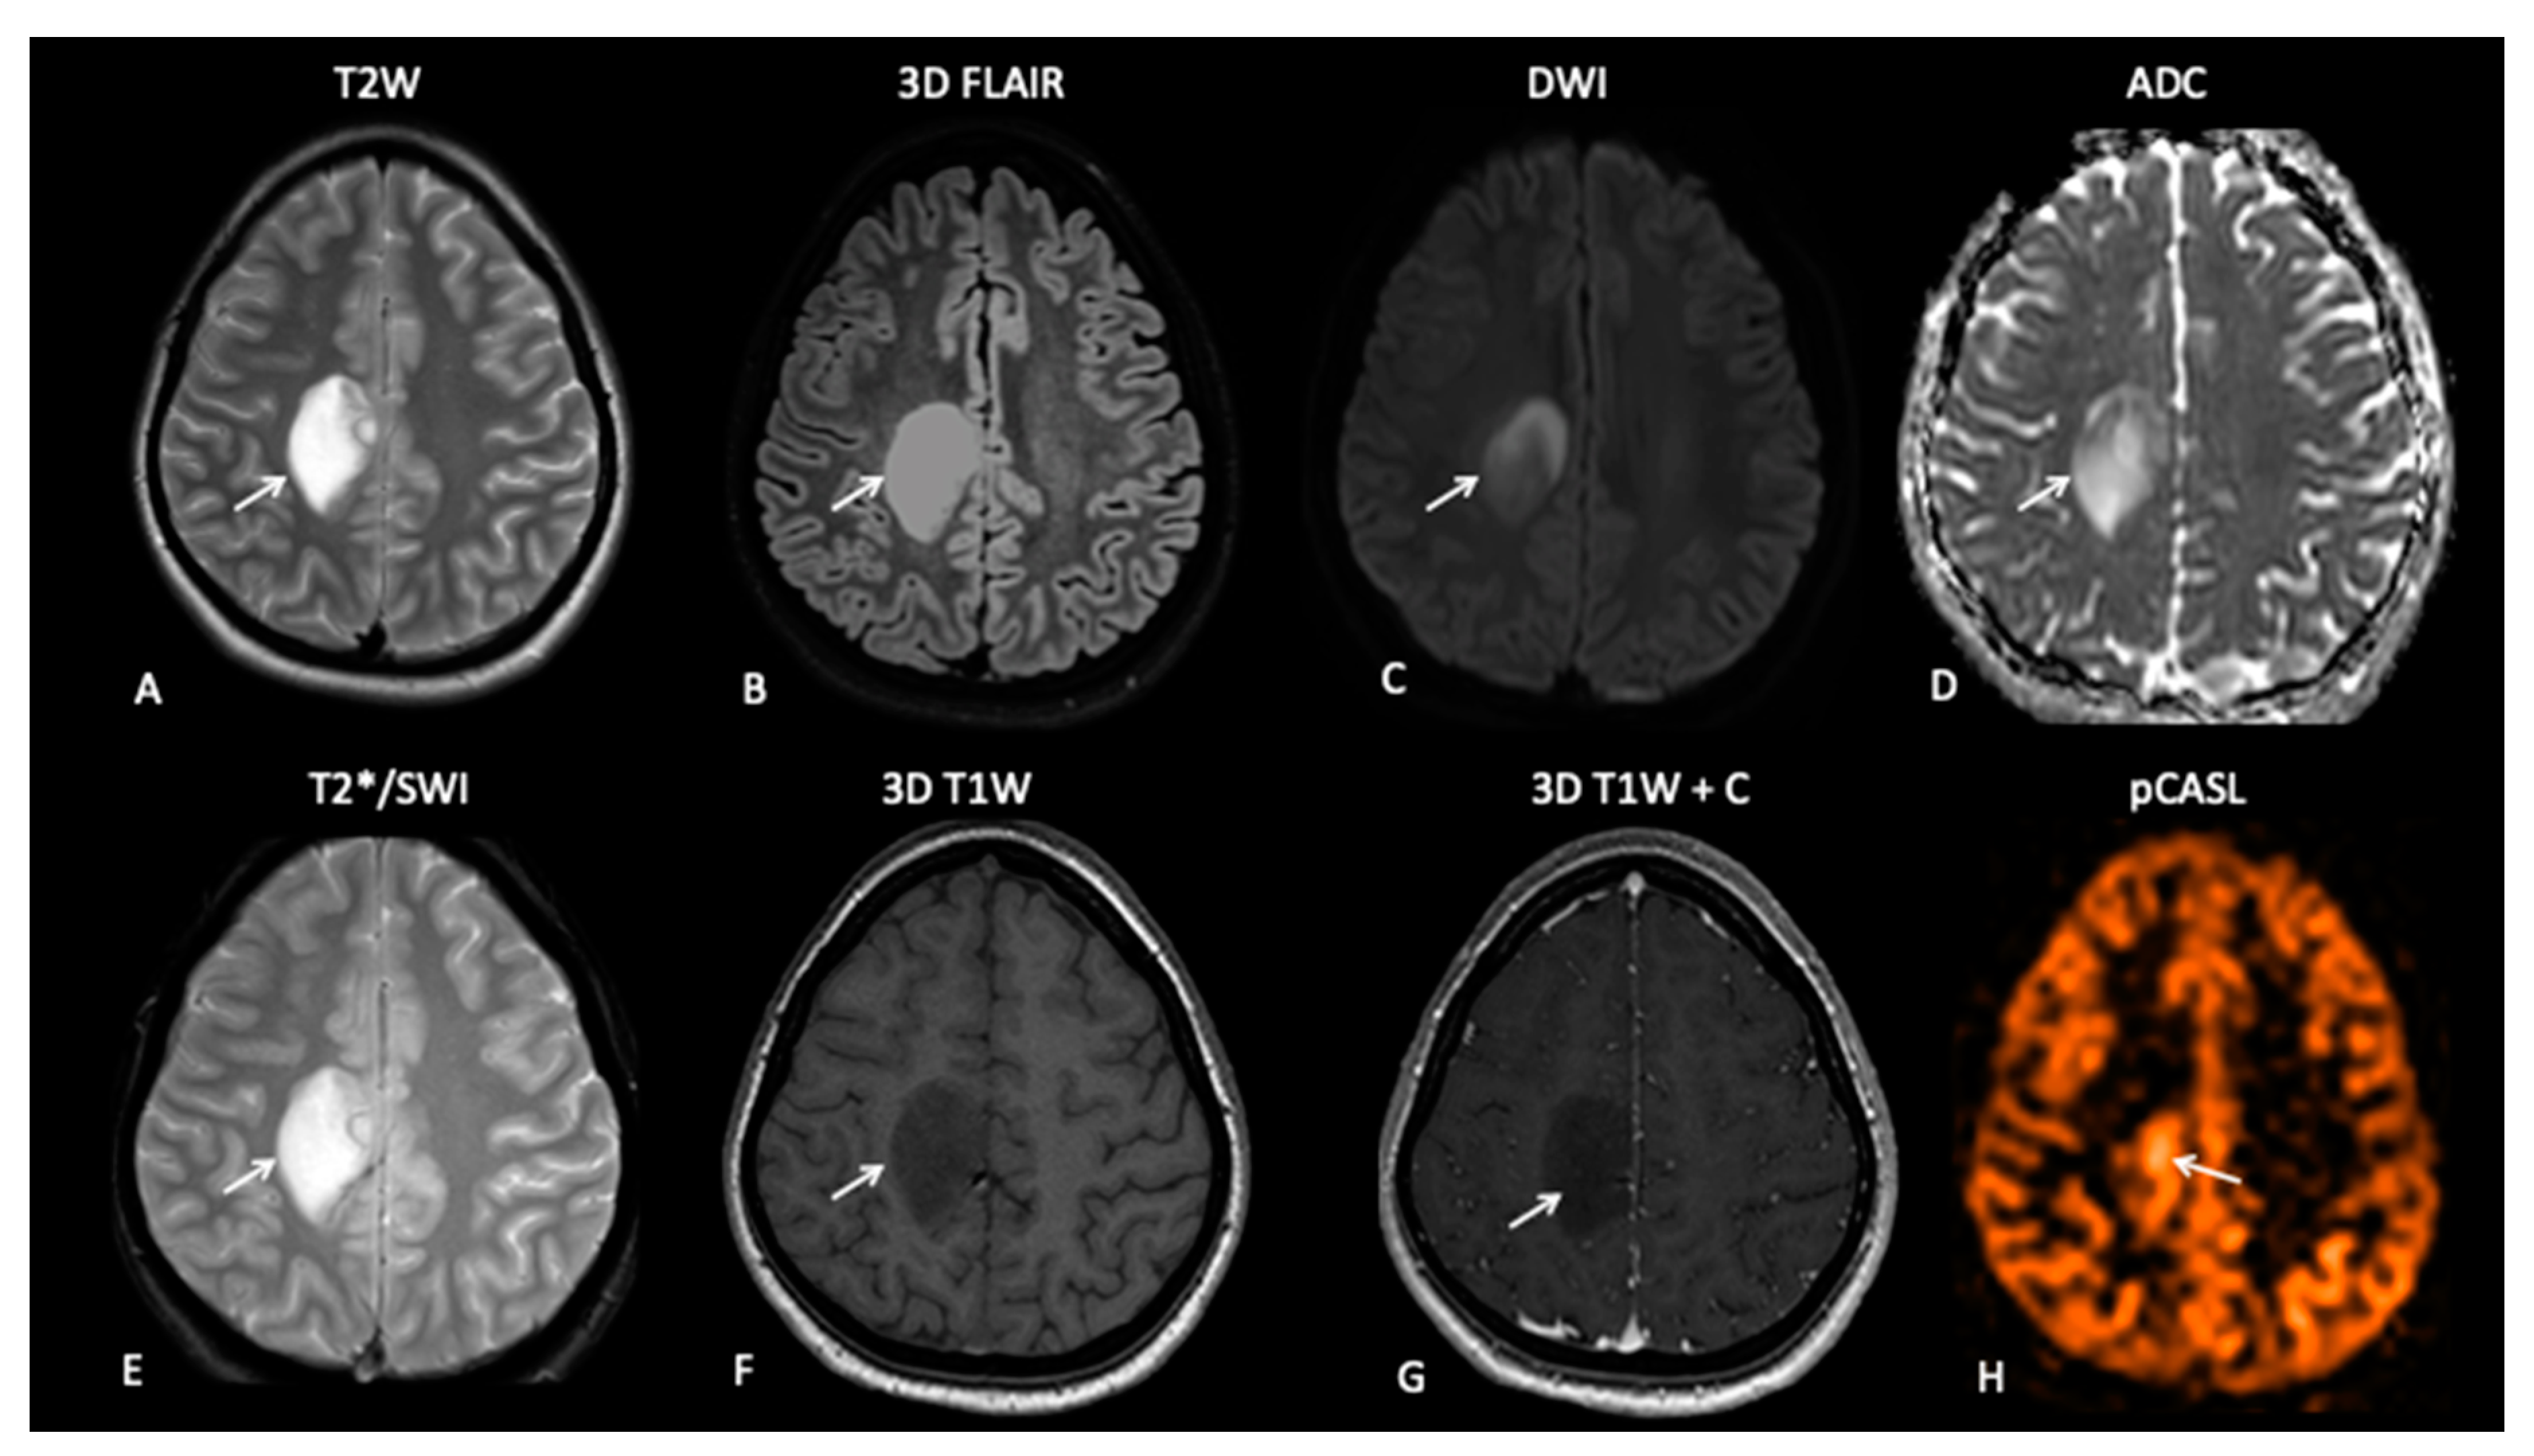

Standard basic minimal anatomical MRI for paediatric brain tumour imaging includes axial fluid-attenuated inversion recovery (FLAIR) and T2-weighted sequences visualizing non-enhancing tumour components, oedema and therapy induced-gliosis, diffusion weighted imaging (DWI) to aid the assessment of therapy response and high-resolution 3D isotropic pre- and post-contrast enhanced T1-weighted sequences to depict contrast leakage from the tumour vessels (Figure 1) [43]. Whilst international standard brain MRI protocols exist for adults [44], no such recommendations exist for paediatric neuro-oncology [45]. At our institution, we follow the adult MRI recommendations but also include a blood sensitive sequence such as T2* or susceptibility weighted imaging (SWI) to depict intra-tumoural haemorrhage and the development of radiation-induced cavernomas, and to depict biopsy tracts [46] and arterial spin labelling (ASL) perfusion to aid in the assessment of gliomas post-treatment [47]. Table 1 demonstrates the parameters for our paediatric/TYA neuro-oncology MRI protocol.

Figure 1.

Nineteen-year-old female presenting with epilepsy. MRI demonstrates a well-defined T2W (A), FLAIR (B), DWI (C) and a hyperintense lesion with a medial border of restricted diffusion on an apparent diffusion coefficient (ADC) map (D). The lesion demonstrates no areas of susceptibility (E) and no pathological enhancement on pre- and post-contrast T1W images (F,G). The appearances are consistent with low-grade glioma, but pCASL perfusion-weighted imaging (PWI) (H) demonstrates medial increased perfusion.

ASL uses endogenous contrast whereby magnetically labelled blood entering the brain can be used to estimate the CBF [57]. The first applications used a long RF pulse simultaneously with a selection gradient, but more recently, a train of short RF pulses combined with a strong gradient has been used (pCASL) [58]. Although, DSC perfusion is most commonly used in clinical practice [59] and numerous studies have demonstrated that rCBV is an early response marker in treated GBMs, pCASL is the favoured PWI technique in paediatric neuro-oncology due to the lack of need for exogenous contrast [60]. pCASL has been shown to correlate with DSC-derived CBF in a study of 15 paediatric gliomas, and numerous studies have demonstrated that increased pCASL-derived CBF is associated with a higher tumour grade [47,52]. pCASL is the preferred PWI technique used at our institution and is part of the neuro-oncology MRI protocol for assessment of treated gliomas (Figure 1). The role of pCASL in the evaluation of treated paediatric gliomas is yet to be established but is the focus of active research.